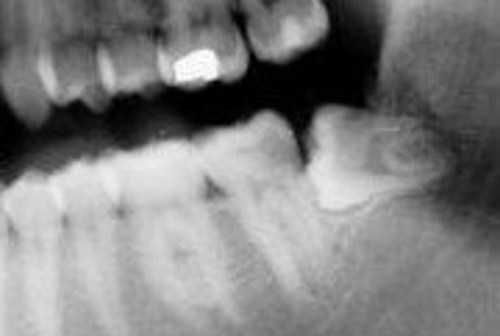

På røntgenbilledet ses en visdomstand, som ligger på tværs og ikke kan komme frem af sig selv. Den skal fjernes, fordi den er kommet delvist frem i munden. Den samler plak, og der er risiko for betændelse nede omkring tanden.